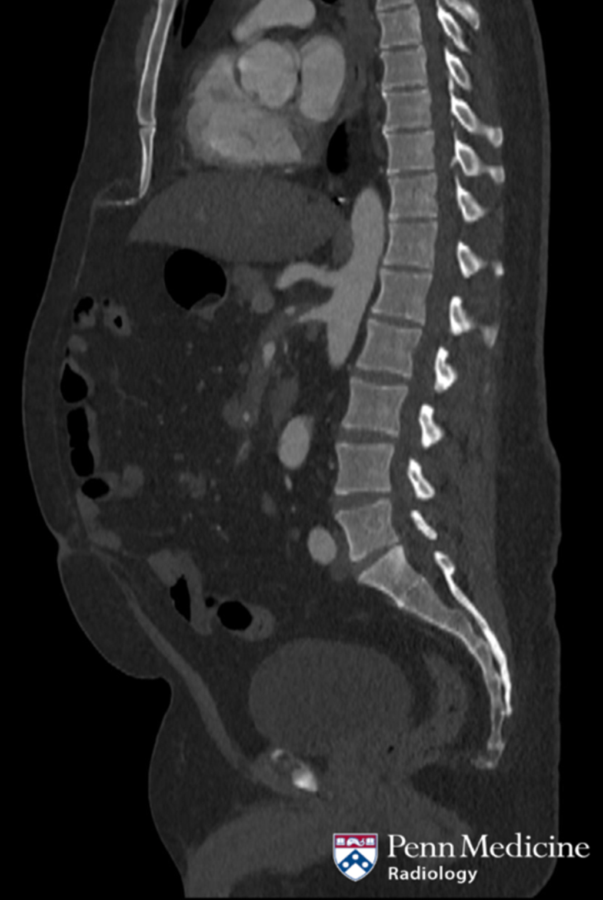

84-year-old man with fever and lower back pain

An 84-year-old man presented with a fever and lower back pain. He had no prior genitourinary, gastrointestinal, respiratory, or systemic symptoms.

Published Date: February 20, 2026